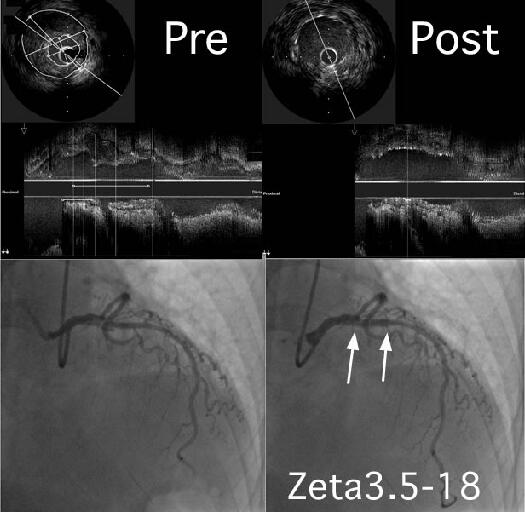

�Q�N�قǑO�ɓ��@�Ōo�������������������𗣂�IVUS���ł��B

59�A�����B30���납�獂�����A�������ǂ�����A�ŋ߂�DM���w�E����Ă��܂����B

�i�����͂���܂���B���]�o���̊���������܂��B

LAD just��soft plaque�̒��ɁA�ۂ�����Ƌ��𗣍o�������܂��B

Zeta 3.5-18��direct stent���܂����Bslow flow�Ȃ���Z���I�����Ă��܂��B